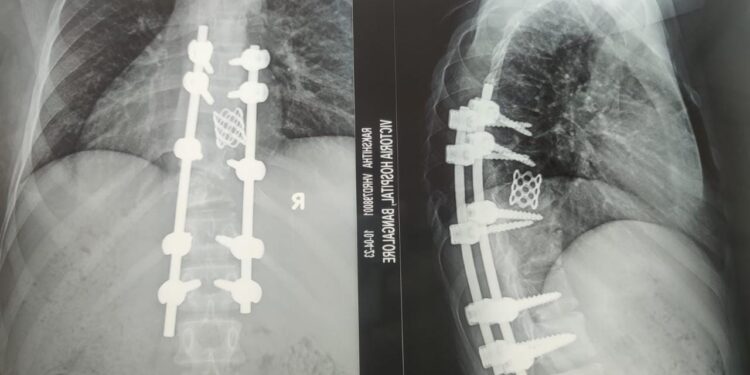

ಬಿಎಂಸಿಆರ್ ಐ ಸಂಸ್ಥೆಯ ವಿಕ್ಟೋರಿಯಾ ಆಸ್ಪತ್ರೆಯ ಅಸ್ಥಿಚಿಕಿತ್ಸಾ ಶಾಸ್ತ್ರ ವಿಭಾಗದಲ್ಲಿ ಸುಸಜ್ಜಿತವಾದ ಸಲಕರಣೆ ಹಾಗೂ ಸೌಲಭ್ಯವಿದ್ದು, ನುರಿತ ತಜ್ಞರುಗಳಿಂದ ಕೀಲು ಮತ್ತು ಮೂಳೆಗೆ ಸಂಬಂಧಿಸಿದಂತೆ ಮಕ್ಕಳಿಂದ ವೃದ್ಧರವರೆವಿಗೂ ಚಿಕಿತ್ಸೆ ದೊರೆಯುತ್ತದೆ. ಅಸ್ಥಿಚಿಕಿತ್ಸಾ ಶಾಸ್ತ್ರ ವಿಭಾಗವು ಎಂಬಿಬಿಎಸ್ ಪದವಿ, ಸ್ನಾತಕೋತ್ತರ ಹಾಗೂ ಫೆಲೋಶಿಪ್ ಶೈಕ್ಷಣಿಕ ಕಾರ್ಯಕ್ರಮಗಳನ್ನು ಕೀಲು ಮೂಳೆ ತಜ್ಞರಿಗೆ ಒದಗಿಸಲಾಗುತ್ತಿದೆ. ಈ ಅಸ್ಥಿಚಿಕಿತ್ಸಾ ಶಾಸ್ತ್ರ ವಿಭಾಗದ ಸಂಯೋಜನೆಯಲ್ಲಿ ಕೃತಕ ಅಂಗ ಜೋಡನೆ ಸಂಸ್ಥೆಯು ಕಾರ್ಯನಿರ್ವಹಿಸುತ್ತಿದ್ದು, ಇದು ಕೈ ಮತ್ತು ಕಾಲುಗಳನ್ನು ಕಳೆದುಕೊಂಡ ರೋಗಿಗಳಿಗೆ ಆಶಾ ಕಿರಣವಾಗಿದ್ದು, ಅವರ ದೈನಂದಿನ ಚಟುವಟಿಕೆಗಳಿಗೆ ಮರಳಲು ಸಹಾಯವಾಗುತ್ತಿದೆ ಎಂದು ಹೇಳಿದರು.

2022-23ನೇ ಇಸವಿಯಲ್ಲಿ ಈ ವಿಭಾಗದಿಂದ 250 ಕೀಲುಗಳ ಮರು ಜೋಡಣೆ, 200 ದೂರದರ್ಶಕ (ಆರ್ಥೋಸ್ಕೋಪಿ) ಶಸ್ತ್ರ ಚಿಕಿತ್ಸೆಯನ್ನು ಆರ್ಥೋಸ್ಕೋಪಿಕ್ ಮುಖಾಂತರ ಭುಜ ಮತ್ತು ಮಂಡಿಗೆ ಆಪರೇಷನ್ ನಡೆಸಲಾಗಿರುತ್ತದೆ. 100 ಅಂಗಗಳ ಪುನರ್ ರಚನೆ ಹಾಗೂ ಅಂಗವೈಕಲ್ಯ ತಡೆಗಟ್ಟುವಿಕೆ ಶಸ್ತ್ರಚಿಕಿತ್ಸೆ, 30 ಬೆನ್ನುಹುರಿ ಶಸ್ತ್ರ ಚಿಕಿತ್ಸೆ ಹಾಗೂ 150 ಪಾದಗಳ ಅಂಗವೈಕಲ್ಯ (CTEV) ಗಳ ಶಸ್ತ್ರ ಚಿಕಿತ್ಸೆಯನ್ನು ನಡೆಸಲಾಗಿದೆ ಎಂದು ಪತ್ರಿಕಾ ಪ್ರಕಟಣೆಯಲ್ಲಿ ತಿಳಿಸಿದೆ.

ವಿಕ್ಟೋರಿಯಾ ಆಸ್ಪತ್ರೆಯ ಅಸ್ಥಿಚಿಕಿತ್ಸಾ ಶಾಸ್ತ್ರ ವಿಭಾಗದಲ್ಲಿ ಒಟ್ಟು 150 ಹಾಸಿಗೆಗಳ ಸೌಕರ್ಯವಿದೆ. ತುರ್ತು ವಿಭಾಗದಲ್ಲಿ ನ ಚಿಕಿತ್ಸೆಗಾಗಿ 20 ಹಾಸಿಗೆಗಳನ್ನು ಹೊಂದಿದೆ. ಪ್ರತಿದಿನ ಮೂಳೆ ಹಾಗೂ ಕೀಲು ಸಂಬಂಧಿತ ಚಿಕಿತ್ಸೆಗಾಗಿ ಸರಾಸರಿ 200 ಹೊರರೋಗಿಗಳು, 10 ರಿಂದ 15 ಒಳರೋಗಿಗಳಾಗಿ ದಾಖಲಾಗುತ್ತಿದ್ದಾರೆ. ಒಟ್ಟು ಐದು ವಿಭಾಗಗಳಲ್ಲಿ 30 ಮಂದಿ ಮೂಳೆ ತಜ್ಞ ವೈದ್ಯರಿದ್ದಾರೆ. ಪ್ರತಿದಿನ 15 ರಿಂದ 20 ಶಸ್ತ್ರಚಿಕಿತ್ಸೆಗಳು ನಡೆಯುತ್ತವೆ.